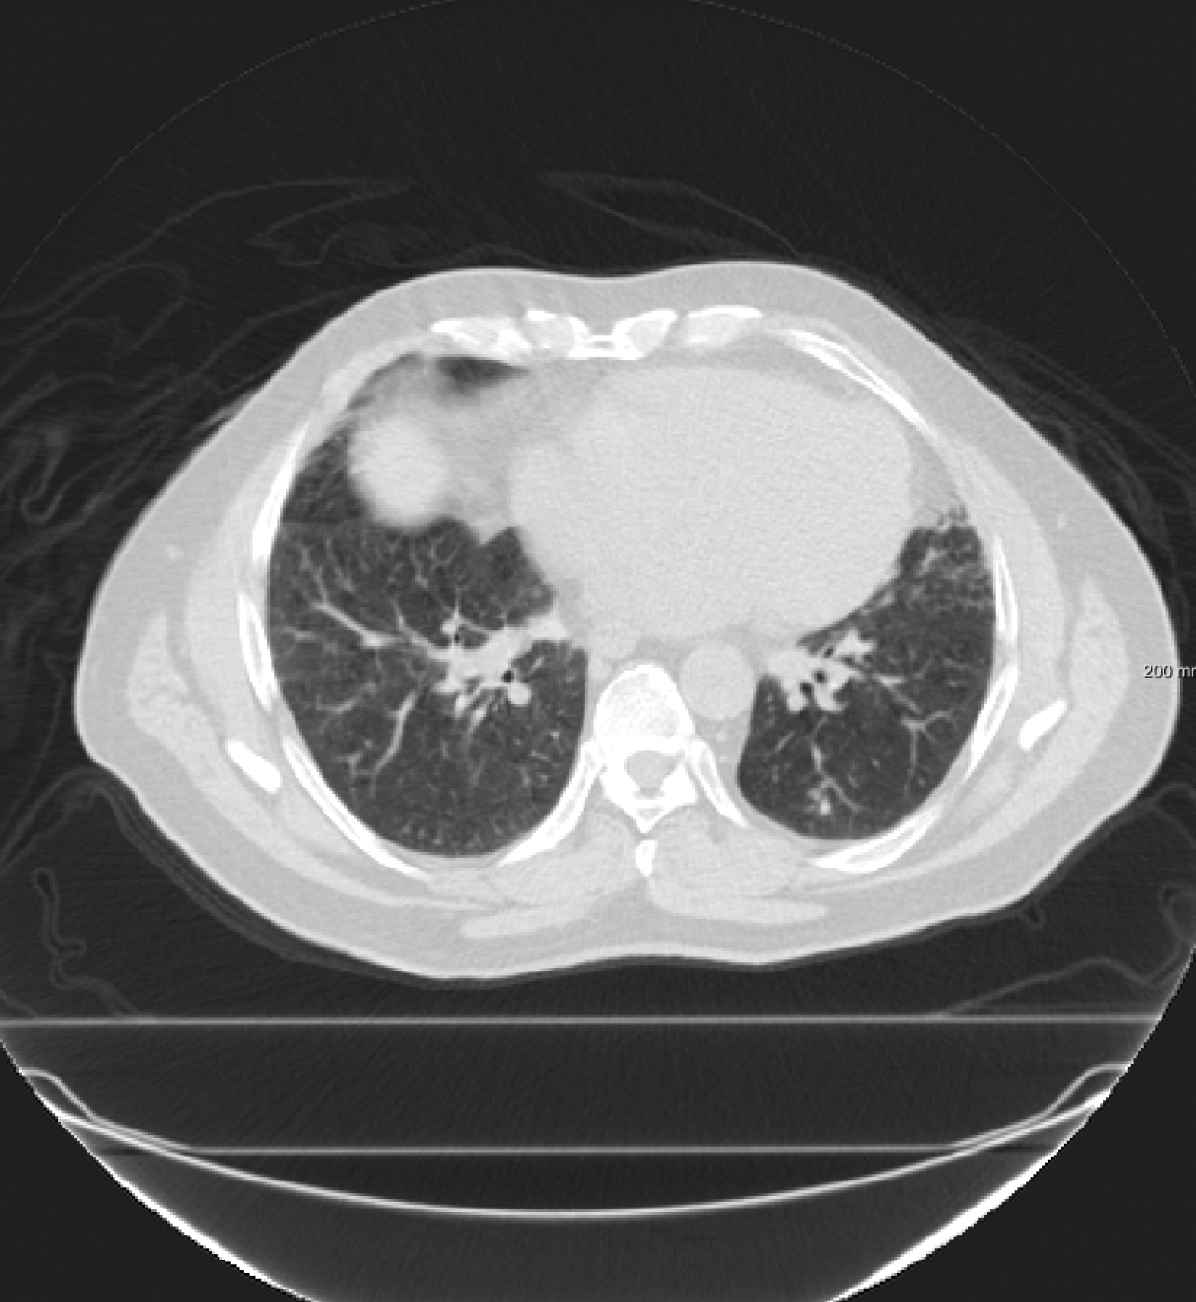

For the SPREAD database, the TRE results with affine and B-spline registration are compared with three versions of RegNet trained using the category “S” (single frequency plus identity), “S+M” (single frequency and mixed frequency plus identity) and “S+M+R” (single frequency plus mixed frequency and respiratory motion plus identity). Since there is no respiratory motion in the SPREAD data, adding respiratory motion did not improve the performance of the registration. Adding mixed frequencies did not change the results considerably: there was a small improvement for the cases 1-11, and slightly larger TREs for the cases 13 to 21. The percentage of folding inside the lung masks for the RegNet trained using “S” is also available in Table III, which reports that the percentage of negative Jacobian are small in most cases, especially, when the TRE after affine registration is not very large. A Wilcoxon signed-rank test is performed between the elastix B-spline and other results. It can be seen that in most cases there is no significant difference between B-spline registration and RegNet trained using “S” or trained using “S+M”.

For the DIR-Lab-4DCT database, a comparison between RegNet and affine, B-spline (three resolutions), an advanced conventional registration method using sliding motion (Berendsen et al., 2014) and three other CNN-based methods (Eppenhof and Pluim, 2018; de Vos et al., 2019; Sentker et al., 2018) is available in Table IV. It can be seen that training with “S+M” improved performance slightly with respect to just “S”. Adding the respiratory motion category improved performance substantially, as these are inhale-exhale pairs; this is predominantly caused by the patients where the TRE after affine registration was still quite large. An example visualization is also available in Fig. 5(f), showing that adding the respiratory motion category can align images better in the diaphragm region. The advanced conventional registration method that leverages sliding motion (Berendsen et al., 2014) is still better than RegNet. Note that RegNet was not trained on the DIR-Lab-4DCT data, similar to Eppenhof and Pluim (2018); Sentker et al. (2018). However, de Vos et al. (2019) and Eppenhof and Pluim (2018)-DIR methods were trained on the same database but using cross-validation to report the results. Also note that the results reported in Sentker et al. (2018) are averaged over all phases of DIR-Lab-4DCT (T00 to T10), while the results of other CNN methods (including RegNet) are reported between the maximum inhale and maximum exhale phase (T00 and T50). These reported results are therefore likely somewhat better than the results for T00 and T50 only.